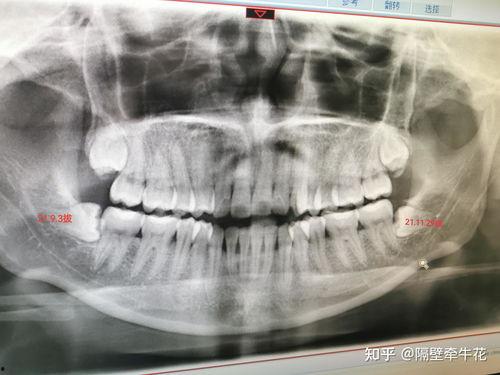

在拔蛀牙之前,牙医会先给你进行口腔检查,确定蛀牙的程度。如果蛀牙较浅,可能只需要进行补牙;如果蛀牙较深,可能就需要拔除。